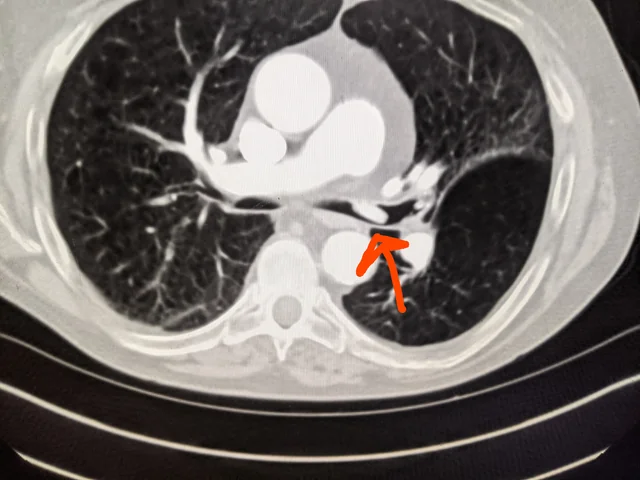

알약먹고 역류해서 약이 올라와서 코끝으로 들어간다음에

기도로 넘어갈수도 있나요?

알약이 기도로 넘어가서 문제가 될 수도 있습니다

기침반사로는 부족했던 것이죠

떡의 경우는 아예 기도를 막아버리는 경우가 드물지 않게 있습니다